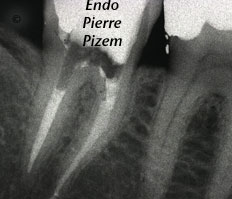

L’OPMI PROergo et la thérapie endodontique d’un système canalaire entièrement calcifié

Cas numero: 465016 Patiente référée pour terminer un traitement endodontique sur une dent au système canalaire